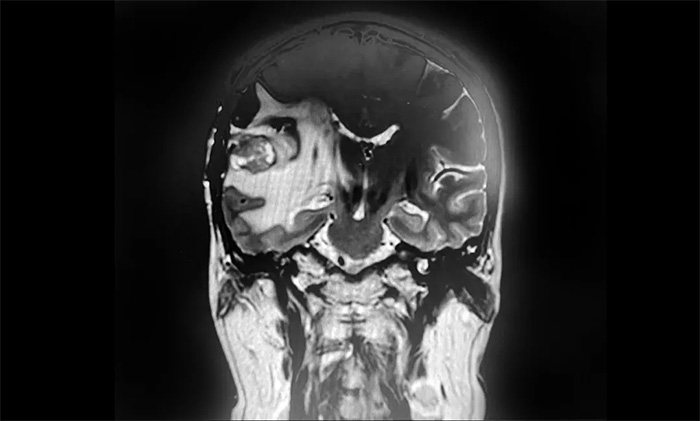

卢云鹤博士为患者进一步完善检查。MR检查示右侧颞叶内见环片状混杂信号,大小约20mm*18mm,强化与水肿明显。周围脑沟、裂显示欠清;右侧侧脑室受压变形,中线结构稍左偏,出现可疑脑膜转移。

▲ MR示右侧颞叶占位,占位效应明显

结合既往病史和影像学表现,卢云鹤博士认为,患者乳腺癌脑转移瘤复发可能性较大。虽然占位本身体积不大,但其水肿带已压迫临近脑室,患者出现头痛头晕症状,应考虑采取合适的方法积极给予治疗。